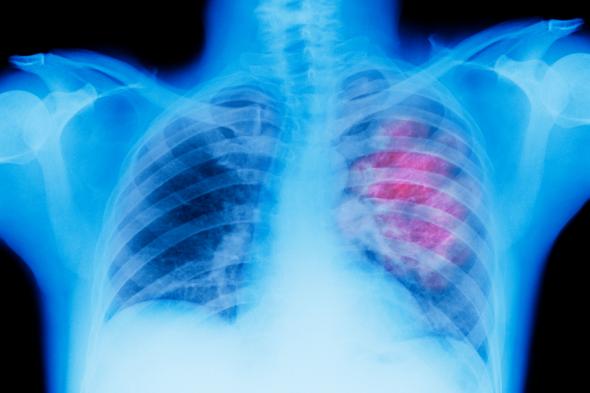

RadiografíaPeter Dazeley via Getty Images

Una investigación del Grupo Español de Cáncer de Pulmón (GECP) ha ratificado el cambio de paradigma en el abordaje de estos tumores en estadios iniciales, sin metástasis, con una estrategia terapéutica que aumenta hasta el 93 % los pacientes candidatos a cirugía y logra erradicar el tumor en el 36,8 % de los casos, lo que favorece el proceso de curación.